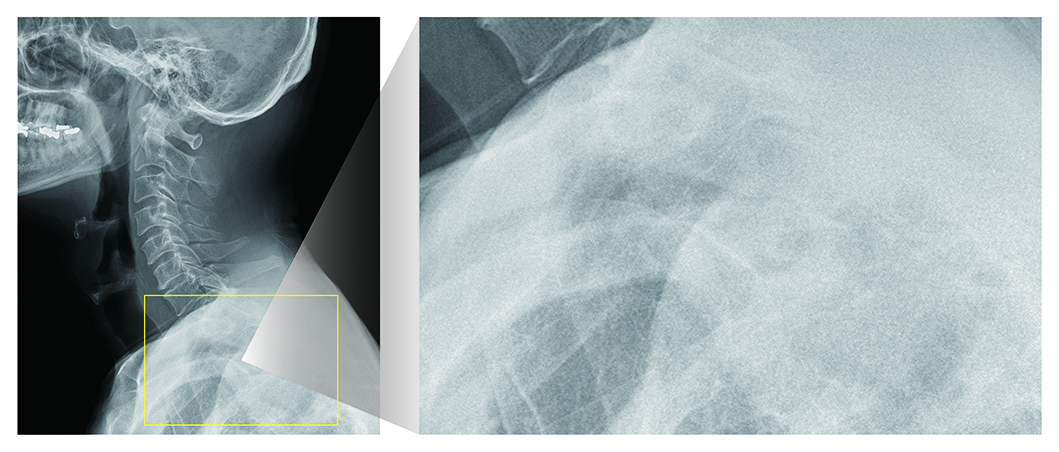

高解像度空間への拡張

AeroDR fineの特徴である100μmを最大限に活かし、周波数強調処理の改良により、高周波領域を忠実に描出可能に。

高解像ならではの微細構造の表現を実現します。